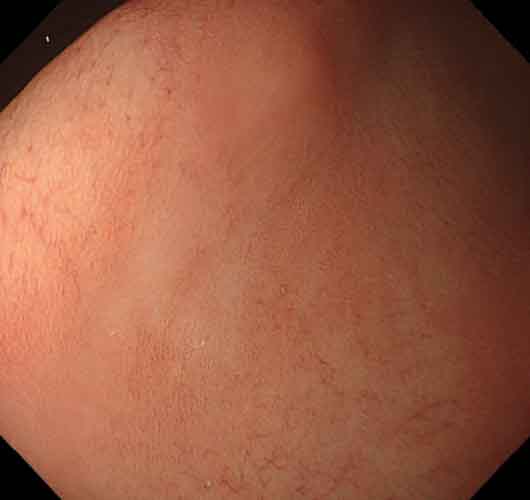

症例3(図3a~d)除菌後に診断された胃底腺型胃癌症例

TXIモード2観察では、病変は胃体部大弯に、周囲に比べて明瞭な褪色を示し、わずかに陥凹した領域として認められる(図3a)。白色光では病変の認識は可能であるが、周囲とのコントラストは弱い(図3b)。NBI観察では、同様に周囲よりわずかに白色調の領域として認識できる(図3c)。更に近接して観察すると、粗造ではあるが胃底腺粘膜の基本構造が明瞭に観察できる(図3d)。

図3 症例3 除菌後に診断された胃底腺型胃癌

• a) TXI モード2

• b) 白色光

• c) NBI

• d) NBI 近接像